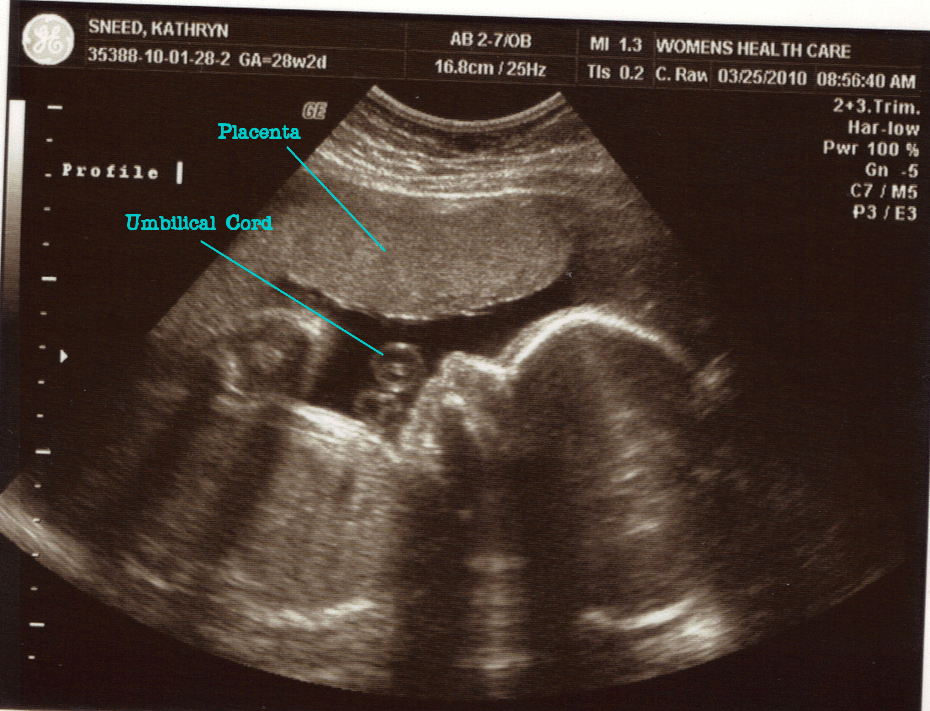

We got to the Doctor’s at 8:45 and waited only a few minutes before they called me for my ultrasound. The reason for this ultrasound was to check something in his heart that they had seen in the ultrasound at 20 weeks. Everything looked great, and they said it was fine. We got to see all four chambers of his heart and she said it looked good!

Adam weighs 2lbs. 12oz. and he has hair!! They showed us his leg bone, and said he is going to be tall! Just like his daddy! (Jon is 6 feet 1 inch.) I am 28 weeks 2 days, but he is measuring about 1 week ahead!